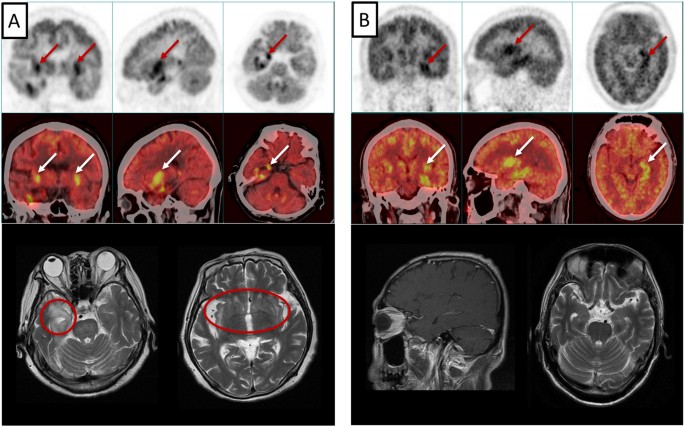

Baseline patient characteristics are shown in Table 1. The median age at presentation was 59 (range 44–64) years with a male/female ratio of 7. Fifteen patients initially presented with disturbance of consciousness, 13 with disorientation, and 12 with seizures. Three patients had dysphagia and one had sensory polyneuropathy. LE patient antibodies, cerebrospinal fluid (CSF) analyses, electroencephalography (EEG), and imaging results are shown in Table 2. Thirteen patients were positive for autoantibodies. GABABR antibodies were found in both CSF and serum samples in seven patients, and solely in serum in one patient. Ten cases had additional antibodies: eight had anti-Hu, and one each had anti-Yo, anti-amphiphysin, anti-ganglioside (GM1). The concordance between serum and CSF was greater for anti-GABABR than for anti-Hu antibodies. Three different kinds of paraneoplastic antibodies were found together in two SCLC patients, reflecting a multifaceted, intraindividual immune response to multiple neuronal proteins expressed in neuroendocrine differentiated tumors. CSF cytology studies showed inflammatory changes with mildly to moderately increased lymphocytes in 8/12 cases. EEGs exhibited focal or global slow waves in 10 patients and sharp waves in two, in one case combined with epileptic activity. MRI T2-fluid attenuated inversion recovery (FLAIR) showed high signal in the bilateral mesial temporal lobes of four patients. PET-CT of nine patients confirmed abnormal metabolism in the temporal lobe, hippocampus, and cerebral cortex. Figure 1 shows MRI and PET-CT images from two cases.

PET-CT and MRI images for two cases. Case 1: 71-year-old female (A) PET-CT showed enhanced metabolism in the bilateral mesial temporal lobe and insula (arrows), and MRI T2 showed high signal in the same location (circles). Case 2: 54-year-old male (B) PET-CT showed abnormal metabolism in the left temporal lobe (arrows), while MRI was normal.